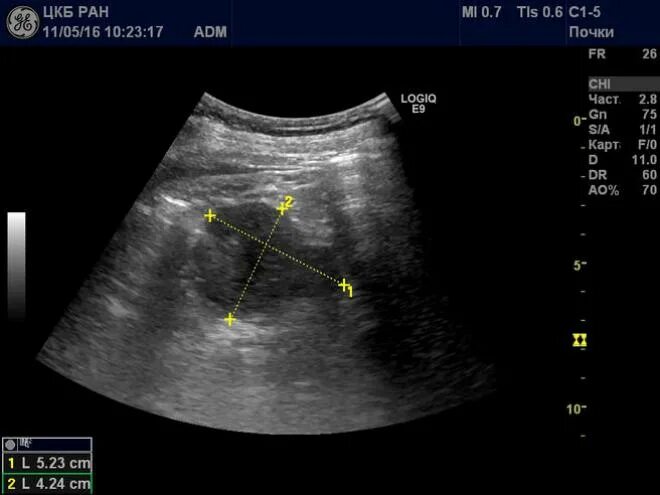

Ультразвуковое исследование забрюшинного пространства